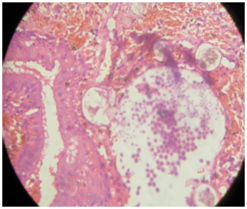

Histopathologic examination of the resected mass showed sporangia covered with multiple layers of keratinized squamous epithelium (Figure 8). The patients exhibited no signs of recurrence at the 6-month follow-up evaluation.

Figure 8 Histopathology picture showing sporangia covered with multiple layers of keratinized squamous epithelium.